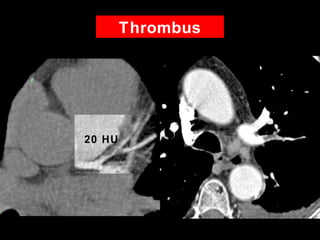

Thrombus

• 42 YOM

• Epigastric chest pain

• Risk Factors

– Hypertension

– Smoker

• No calcium

20 HU